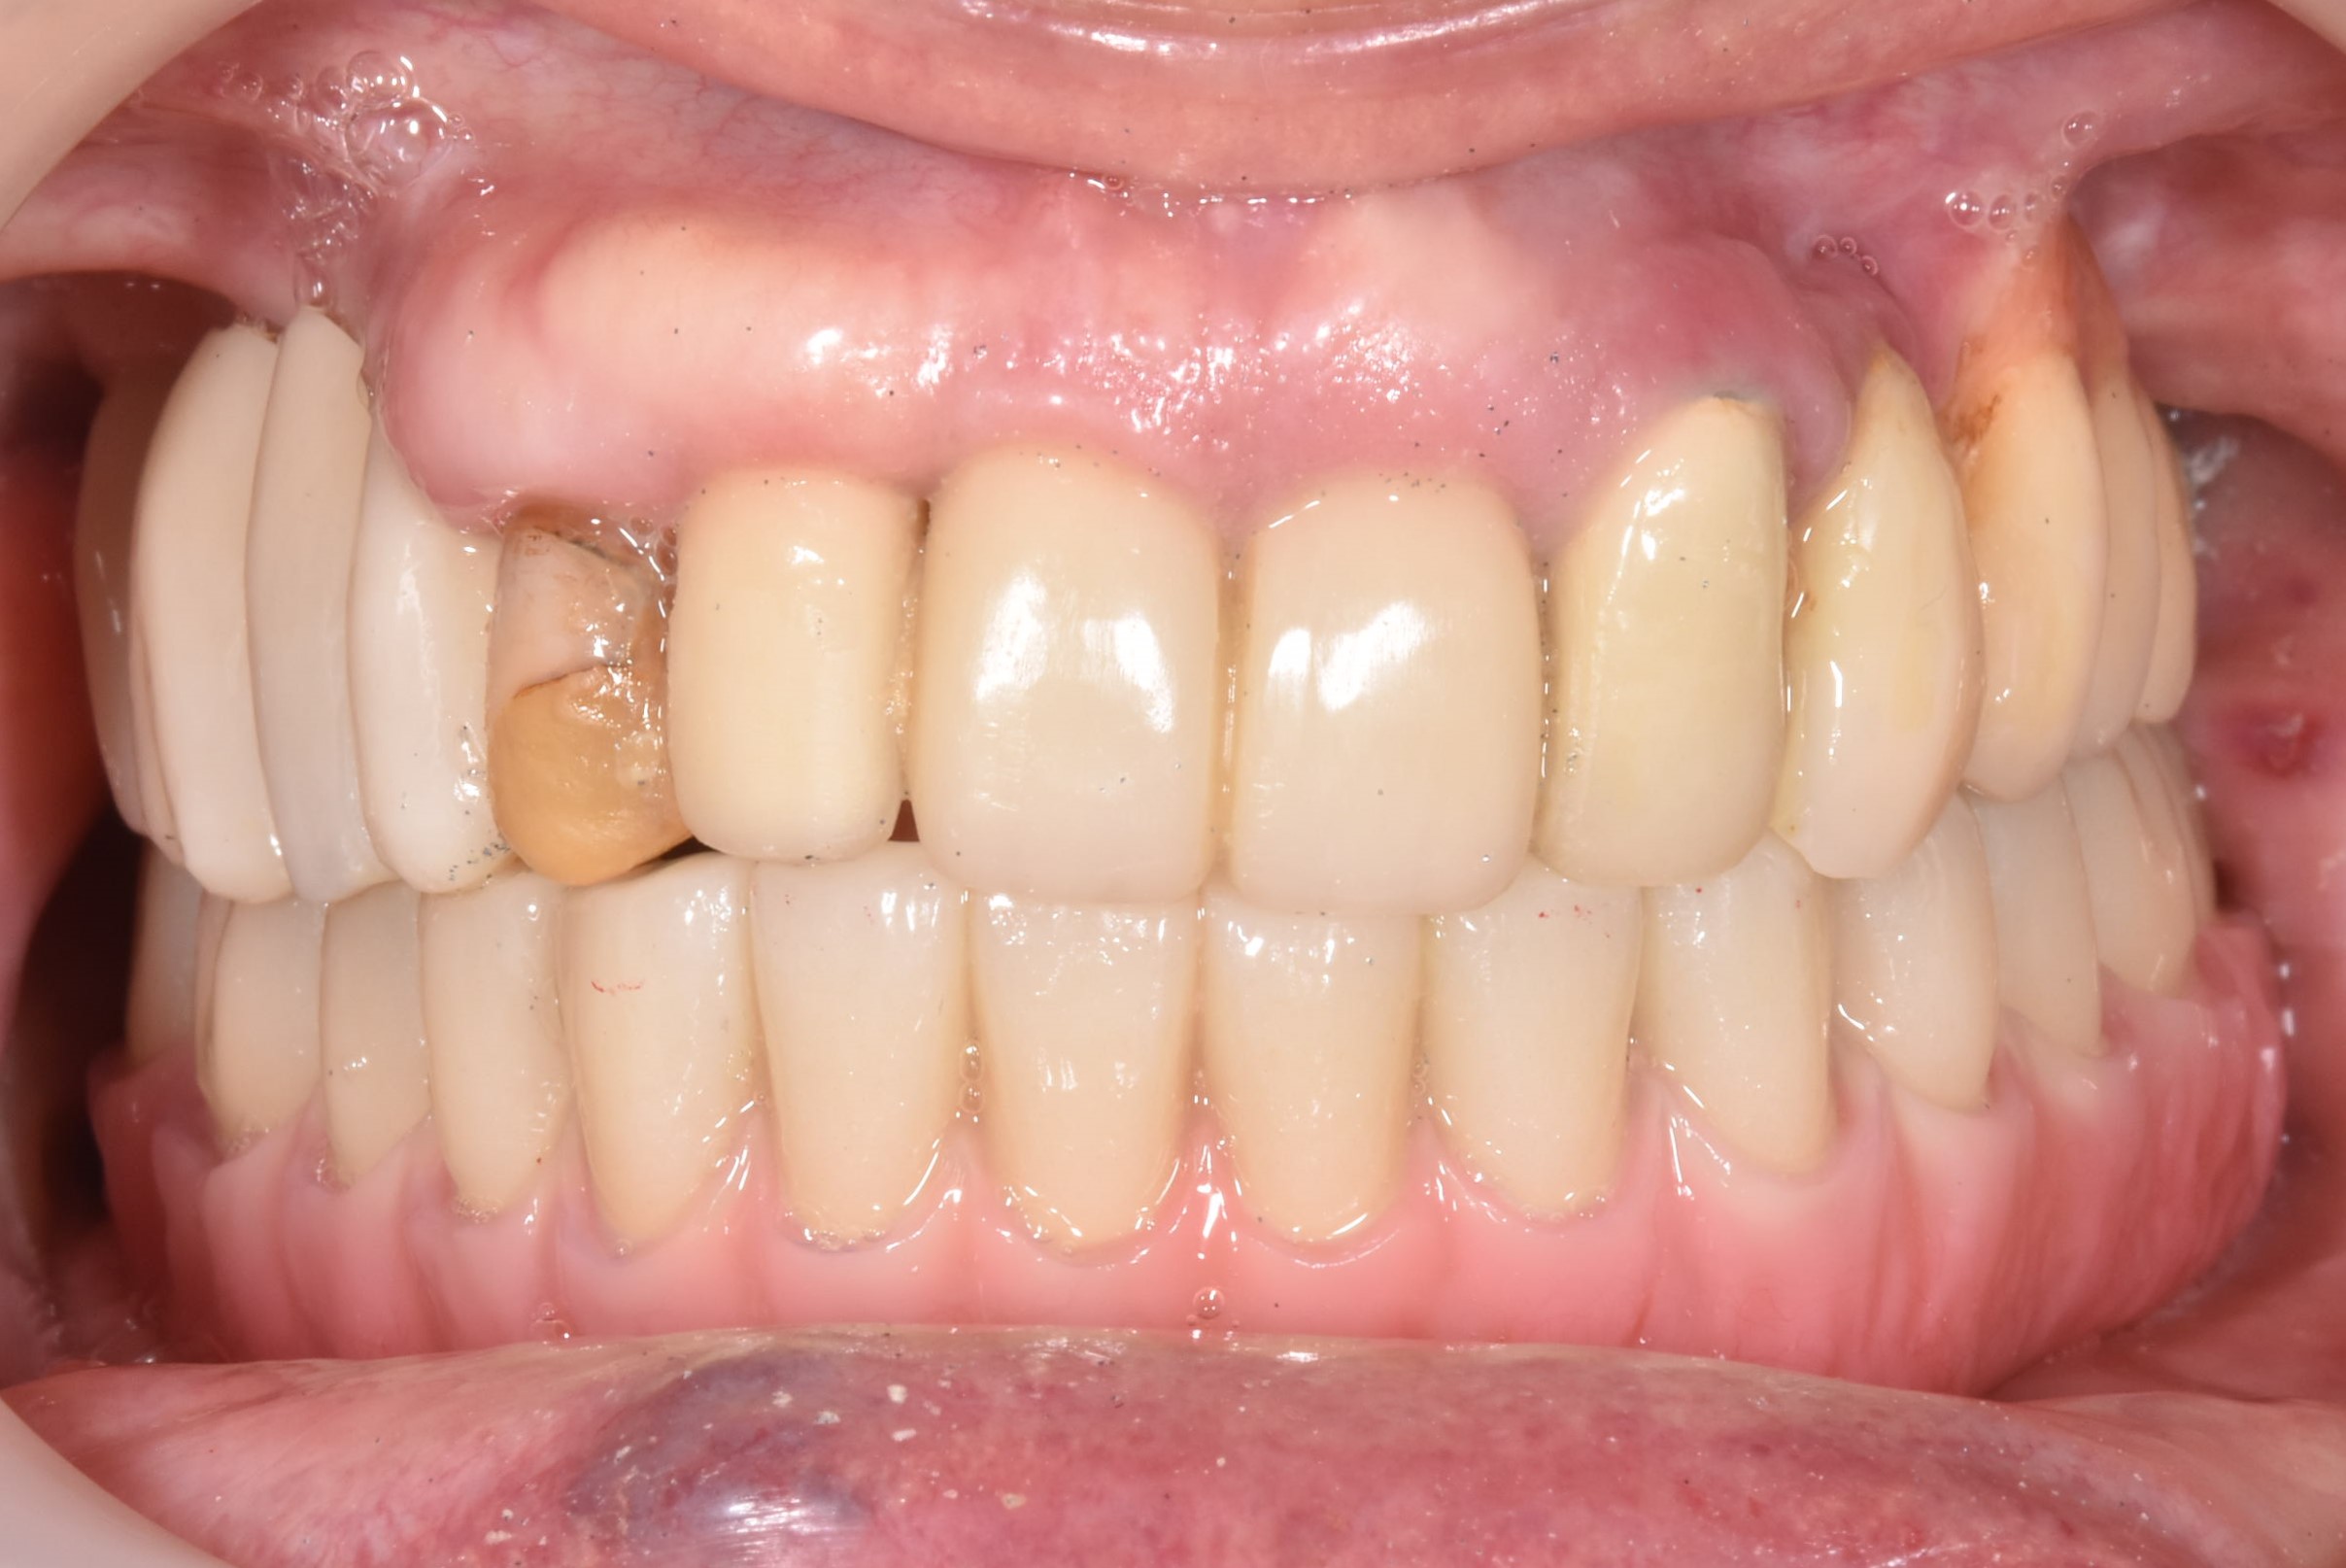

案例-上顎

醫生透過電腦斷層及全口X光照片評估骨頭狀況決定植入的植體數量、寬度以及深度

當天有臨時假,鎖上並封填

大約3-4的癒合時間,把臨時假牙取下

鎖上正式假牙

完成!